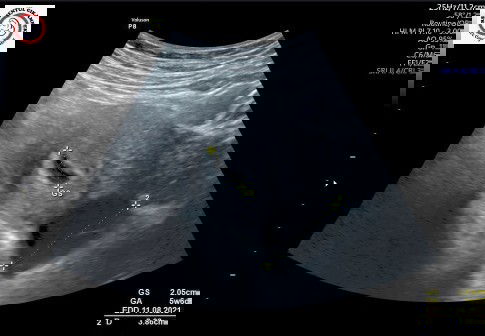

Saya juga ada kista, bund. Ketauan ada kista pas usg pertama uk 4w, belum keliatan kantungnya, palah keliatan kistanya 😥 dokter bilang aman, ngga perlu ada tindakan. Sekarang jalan 13w, Bismillah semoga sehat semuanya. Semangat,, bunda ngga sendirian 😇